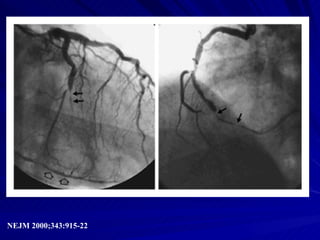

Angiografía de la Angina Inestable

Angiografía de laAngina Inestable